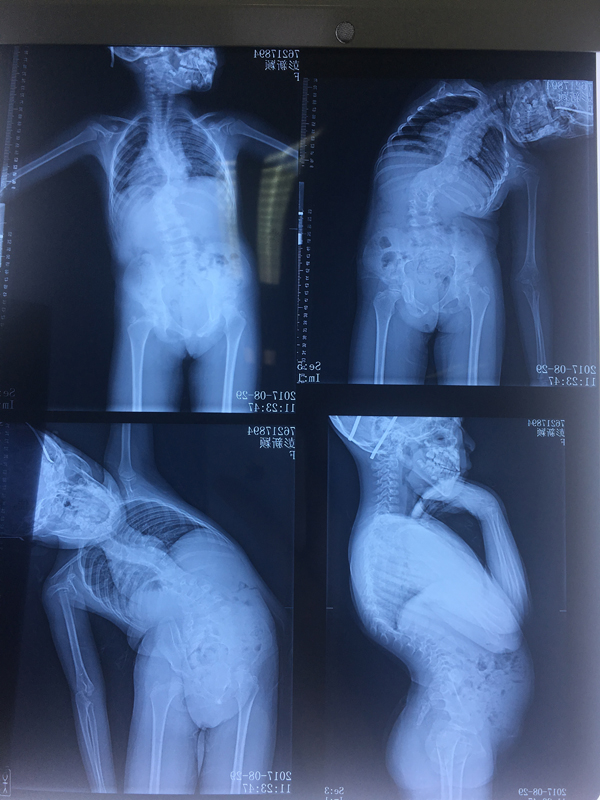

小颖的脊柱侧弯X光片

“小颖的先天性脊柱侧弯病情比较严重,其中胸8半椎体分解不全,胸11半椎体畸形,两个阶段半椎体之间的弯度在90度左右。” 颜滨指着小颖早前的x光片说,手术主要有三个难题,一是小孩年纪太小,病情发展速度会很快,同时也要考虑到小孩未来的骨骼生长问题,此外,小孩身子瘦,能否耐受手术也是一个问题,这些都需要进行相关检查。